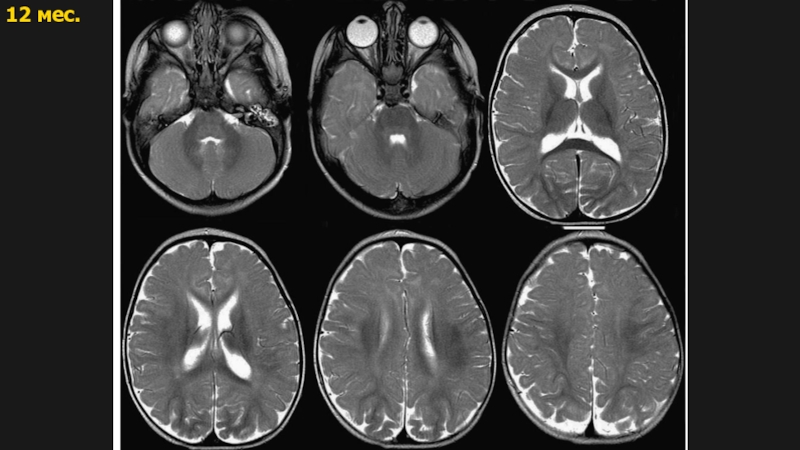

Слайд 1812 мес

2 года

12 мес2 года